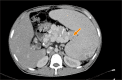

Methods: This was a retrospective cohort study of patients with NCPH who underwent PSRS between 2014-2020 in JIPMER, Puducherry, India. CP was performed in patients with a long tail of pancreas, with the tip of pancreatic tail extending up to splenic hilum on preoperative CT. Perioperative parameters and shunt patency rate of patients who underwent PSRS with CP (Group A) were compared with patients undergoing conventional PSRS (Group B). Statistical analysis was performed using the Mann-Whitney U test and χ2 test.